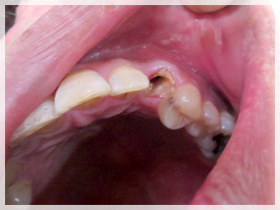

40代女性

ちゃんと噛めない、歯が弱いから治したい、歯が無いからなんとかしたい、歯を見せて笑いたい、顎が痛い

*上はセラミックのブリッジとワイヤーのないアタッチメントを用いた薄いメタルプレー と(金属の入れ歯)に。

*下はセラミックのブリッジを左右にそれぞれ入れる事に。

1:まずは歯周病の治療を徹底的に行い歯をできるだけいい状態にしてから、同時に治療が終わるまでの仮の歯(仮歯)を作り噛める様にしました。上の歯は残せない状態でしたので1本だけ抜歯をしました。

2:上下の仮歯にした状態で、この患者さんに合っているか?を全てのチェックして調整しました。

3:最終的に決めた材料に置き換えました。

ちゃんとなんでも噛める様になったのと、審美的回復にも大変満足していただきました。

口元のハリも出て、唇がちゃんと出てきたと喜んでいただきました。

また顎の痛みもこの頃には無くなりました。良かったです。